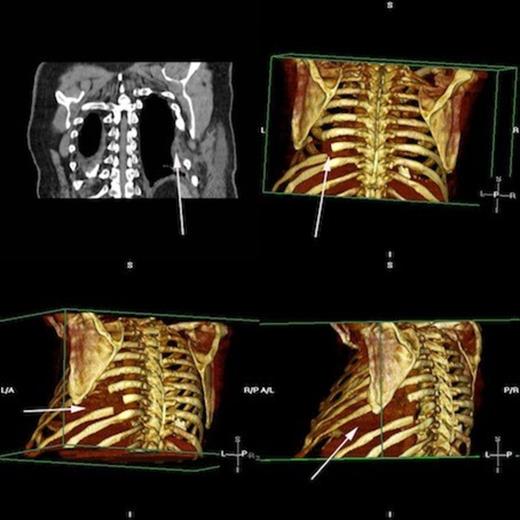

A CXR scan was performed which illustrated atelectasis at his left lung base. A subsequent CT demonstrated intercostal lung herniation alongside fractured sixth, seventh and eighth ribs, arising as a result of chest wall deformity (figure 1). Images were subsequently reconstructed by a clinical radiologist to fully demonstrate the skeletal pathology. (figure 2)

Rendered images of fractured ribs 6, 7 and 8 Arrowheads demonstrating fractures of the left 6th, 7th and 8th ribs. * = site of skeletal defect and subsequent site of pulmonary herniation